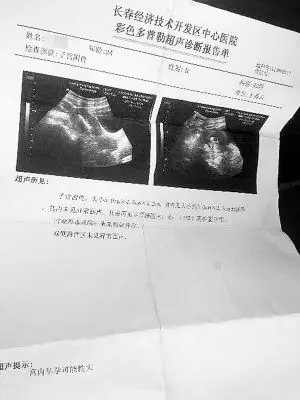

我到底怀没怀孕 请给我个准信儿(图)